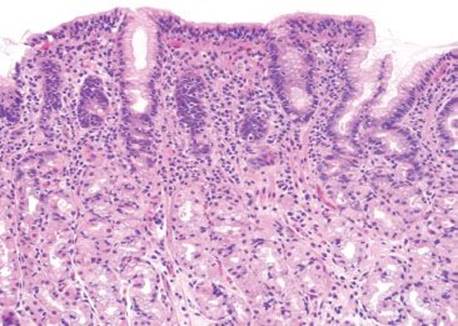

Lymphocytic gastritis differs from chronic gastritis by the presence of increased intraepithelial lymphocytes (IELs), defined as more than 25 intraepithelial lymphocytes per 100 epithelial cells (Figs. 2.120–2.126).38,91–97 The term “lymphocytic gastritis” was originally used to describe the histologic counterpart to “varioliform” gastritis (i.e., thickened rugal folds and erosions), but subsequent studies have shown this association in only 3.9% to 30% of cases. More commonly, the endoscopic image shows erythema but up to 50% of patients have a normal endoscopic appearance. Although the etiology of the inflammation remains unknown in up to 20% of cases, common associations include infection (e.g., Helicobacter, HIV), celiac disease and other immune-mediated disorders (common variable immunodeficiency, Crohn disease, lymphocytic enterocolitis), medications, and neoplasia (Figs. 2.127–2.142).98 As a result, recognition of the lymphocytic gastritis pattern can serve as an important red flag to the underlying diagnosis and, consequently, lead to effective therapy with resolution of symptoms. The changes affect the entire stomach, but intraepithelial lymphocytes are most evident in the oxyntic mucosa, and are more prominent in the superficial epithelium than the glands. Most cases show expansion of the lamina propria with a mixed lymphoplasmacytic inflammatory infiltrate, in addition to the intraepithelial lymphocytosis (Fig. 2.121). Regenerative and hyperplastic changes in the surface epithelium may be present, analogous to the surface changes seen with intraepithelial lymphocytosis of the small and large bowel. Immunolabeling identifies these as CD3+ T cells, with about 80% showing a cytotoxic/suppressor CD8+ phenotype. Most patients respond to treatment of their associated condition, when a known etiology is present (i.e., successful eradication of Helicobacter usually leads to reduced symptoms and decreased inflammation in biopsies, and adherence to a gluten-free diet typically results in clinical and histologic improvement in patients with celiac disease). Others advocate empiric Helicobacter eradiation, even in Helicobacter-negative patients. In general, immunosuppressive medications are reserved for those who fail gluten withdrawal and whose intraepithelial lymphocytosis involves the stomach, small, and large bowel. Untreated lymphocytic gastritis may persist for years, although spontaneous remission has been reported.

Figure 2.121 Lymphocytic gastritis pattern. The changes of lymphocytic gastritis are often prominent enough that they can be identified at scanning magnification, obviating the need for intraepithelial lymphocyte counts. The IELs usually affect the entire stomach but are more evident in the oxyntic mucosa and are more prominent in the superficial epithelium as compared to the deeper glands. Note the diffuse mixed inflammatory infiltrate in the lamina propria.

Figure 2.122 Lymphocytic gastritis pattern. There is a prominence of IELs in the surface epithelium, with expansion of the lamina propria by a mixed chronic inflammatory infiltrate that is plasma cell rich. This case had no demonstrable Helicobacter organisms, but additional clinical testing was suggested based on histologic findings.